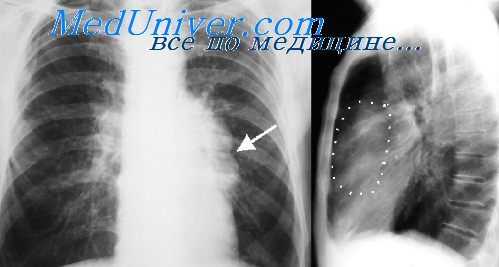

На рентгенограммах плотные включения (чаще всего это бесформенные известковые или костные образования) имеют вид неправильной формы и различной величины интенсивных патологических теней на фоне тени кисты. Реже выявляются тени, обусловленные наличием в дермоиде сформировавшихся костных тел (зубы, челюсти, трубчатая кость). Обнаружение этих элементов, особенно зубов и челюсти, считается патогномоничным рентгенологическим признаком дермоидных кист и тератом. По мнению С. М. Демкова, костные включения чаще указывают на тератому.

Мы наблюдали два случая дермоидных образований, содержащих бесформенные плотные включения. В обоих этих наблюдениях обнаружение плотных включений при наличии других характерных клинических и рентгенологических симптомов является достоверным признаком дермоидных образований — тератом.

2) овальная форма затемнения с четкими правильно выпуклыми, но нередко волнистыми или бугристыми контурами;

3) наличие в ряде случаев плотных включений или обызвествления капсулы, что можно считать почти патогномоничными симптомами дермоидных кист и тератом.